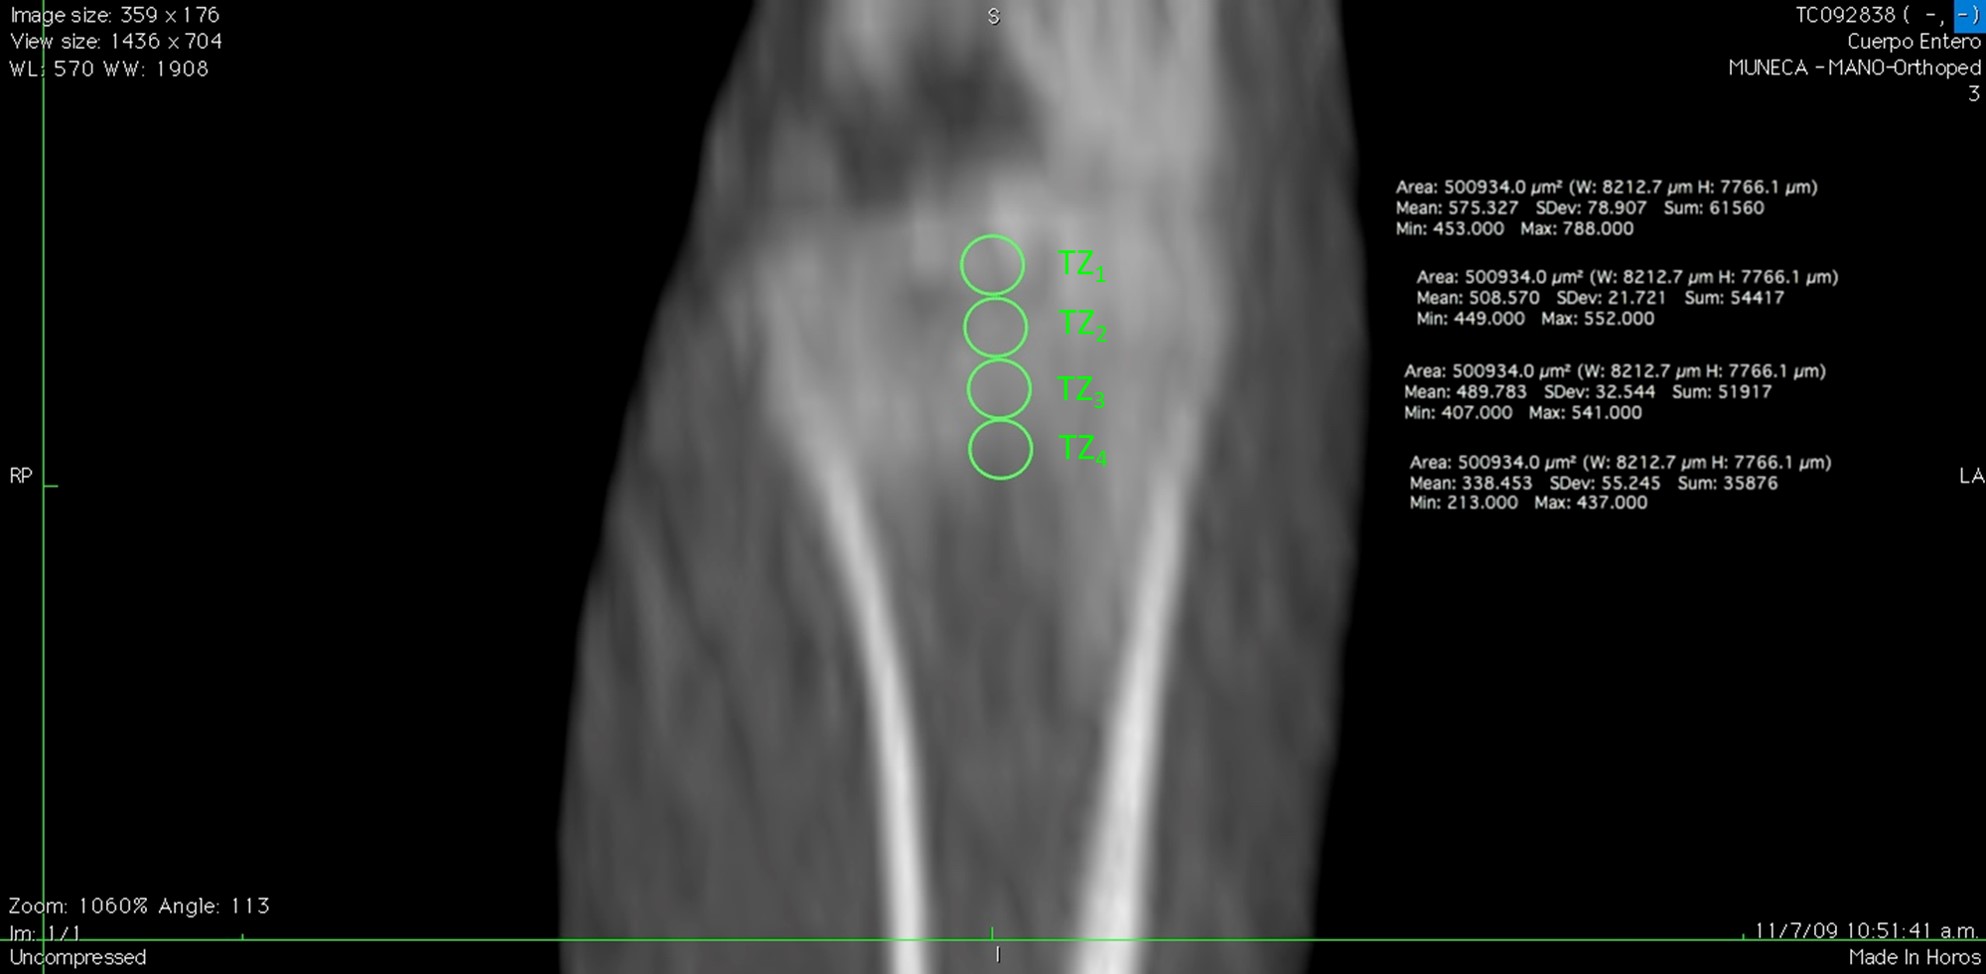

Philips Brillance 64 CT equipment placed in "Sagrada Familia" Clinic (ENERI, Argentina) was used. Images obtained by Multi Slice-Quantitative Computed Tomography (MS-QCT) were analyzed with eFilm Workstation 2.1 program and measurements in Hounsfield units (HU) acquired bone density data based on QCT principles. The acquisition was made with the animal in prone position, locking of the legs and intraperitoneal anesthesia (0.5 mg Xylazine + 8.75 mg Ketamine/ 100 g rat Wt). At 7w an exploration of the whole body of each animal was achieved, using high resolution protocols adapted to small animals, standardized in preliminary studies [18]. Based on morphological and histological positioning that was to be compared [19] measurements were performed with the HOROS program under environment McIntosh, multiplanar review for drawings to display sagittal, coronal and axial positions, taking as reference tibial plate and placing a centered parallel to the cortical and a perpendicular intercondylar line as guides (Figure 1). In search for alignment of dishes, angles were used with a variation of ± 25°. Thickness was 0.45 mm and a ROI (Region of Interest) for the measurement of density of 0.5 mm2 area. In this way four tibial zones (TZ1-4) were defined, from the tibial plate towards the metaphysis (Figure 2). The tibial zones selected had to be standardized and aimed to survey from growth plate cartilage (TZ1) to the central area of subchondral bone, across primary and secondary cancellous bone (TZ2-4) to compare with histomorphometric parameters. Measurements were all carried out by one operator and verified by a second operator under the same environment HOROS. Each animal data resulted from the average of the measurements of both operators.

Figure 2: Image shows standardized measurements performed with the HOROS program under environment Mc Intosh. Thickness was 0.45 mm and a ROI (Region of Interest) for the measurement of density of 0.5 mm2 area. In this way four tibial zones (TZ1-4) were defined, from the tibial plate towards the metaphysis. View Figure 2